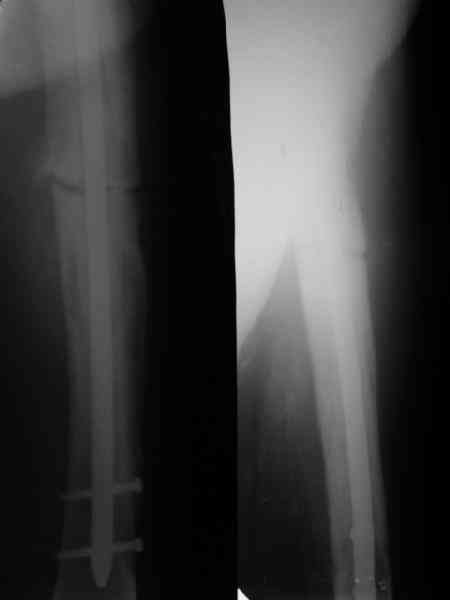

Пациент 82 лет, поступил через 5 мес. с несросшимся переломом после открытого интрамедуллярного остеосинтеза. Выполнили реостеосинтез стержнем 12 мм. ( мах. доступного нам в 2003 г.) Через 4 мес динамизация. В течении 2х лет сращения нет, тем не менее конечность опорна (ходит с тростью). От очередного реостеосинтеза отказались из-за сопутств. патологии.

Еще один пример. Пациентка с юга России, прислала рентгенограммы через год. На сегодня прошло 2 г. 8 мес. после операции. Несмотря на не очень убедительный процесс сращения, пациентка ходит. Учитывая остеопороз при Педжете, решили, что динамизировать вообще не нужно.

При переломах на фоне болезни Педжета металлоконструкция часто служит эндопротезом, несущим нагрузку. Динамизация индивидуальна,- по рентген-динамике. Основной упор- на медикаментозную терапию- см. канд. дисс. Колондаева А.Ф.

Стержень можно было бы поставить подлиннее.